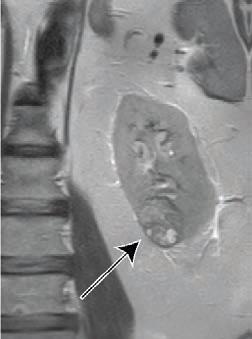

Leesburg, VA, July 22, 2021--According to ARRS' American Journal of Roentgenology (AJR), the standardized non-invasive clear cell likelihood score (ccLS)--derived from MRI--correlates with the growth rate of small renal masses (cT1a, <4 cm) and may help guide personalized management.

Extracted from clinical reports, "the ccLS scores the likelihood that the small renal mass represents clear cell renal cell carcinoma, from 1 (very unlikely) to 5 (very likely)," explained corresponding author Ivan Pedrosa from the University of Texas Southwestern Medical Center at Dallas. "Small renal masses with lower ccLS may be considered for active surveillance, whereas small renal masses with higher ccLS may warrant earlier intervention."

Among 389 small renal masses in 339 patients (198 men, 141 women; median age, 65 years) on active surveillance that were assigned a ccLS on clinical MRI examinations, those with ccLS4-5 grew significantly faster (9% diameter, 29% volume yearly) than those with ccLS1-2 (5% diameter, p<.001; 16% volume, p<.001) or ccLS3 (4% diameter, p<.001; 15% volume, p<.001).